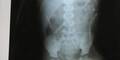

Der Mann sei von seiner Geliebten zu der grausamen Tat angetrieben worden, die ihm geraten habe, seinen Stiefsohn durch das Ritual zu töten, sagte der Polizist. Das Kind war am Sonntag mit Erbrechen und Schmerzen ins Krankenhaus gebracht worden, wo die entsetzten Ärzte beim Röntgen die Nadeln entdeckten.

Der Bub lag am Mittwoch weiter auf der Intensivstation. Jetzt prüften die Ärzte seinen Zustand, um möglicherweise die Nadeln herauszuoperieren, die am dichtesten an lebenswichtigen Organen säßen: "Aber das könnte noch gefährlicher sein, als sie einfach steckenzulassen", sagte eine Sprecherin.